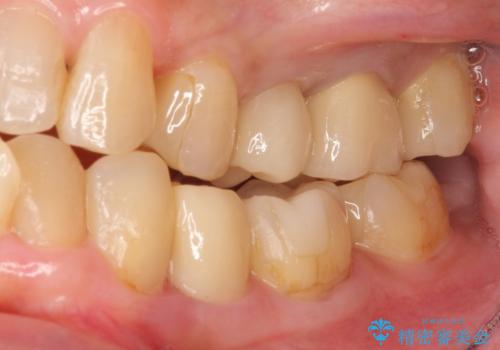

特に割れている所見はなかったため、根の治療から被せ物まで治療を行いました。

奥の銀歯のやりかえも希望されたため、セラミッククラウン、インレーにする治療をしています。

左上6番のアンレーは、歯の破折を防ぐためにクラウンとしました。